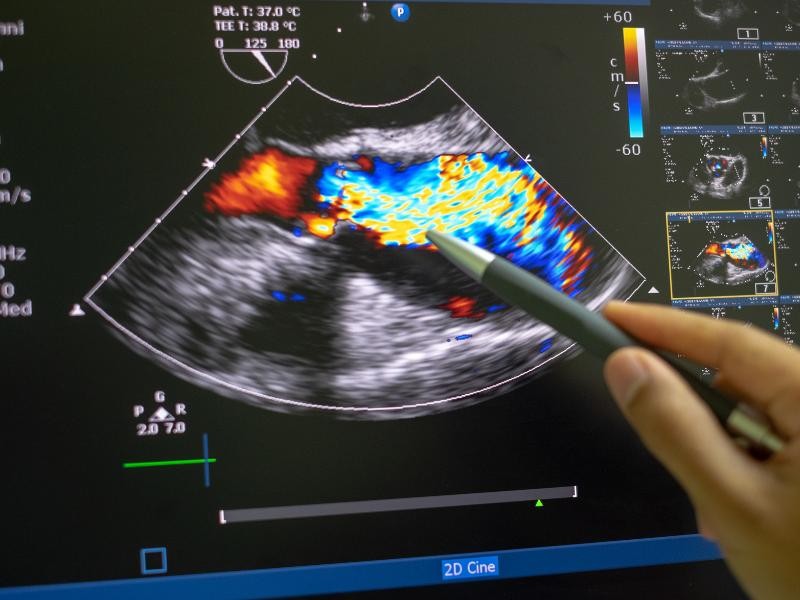

O Ecodoppler de Aorta e Ilíacas é um exame de ultrassonografia que utiliza ondas sonoras para gerar imagens detalhadas da aorta abdominal e das artérias ilíacas, avaliando o fluxo sanguíneo e identificando possíveis obstruções ou dilatações. Esse exame é fundamental para um diagnóstico preciso e para a definição do melhor tratamento vascular. Na Instamed, garantimos um exame seguro e preciso para um diagnóstico confiável.

O exame de Ecodoppler de Aorta e Ilíacas é realizado com o paciente deitado, utilizando um transdutor que emite ondas sonoras para capturar imagens detalhadas da aorta e das artérias ilíacas. Esse exame é indolor, não invasivo e não requer contraste, proporcionando segurança ao paciente. Na Instamed, utilizamos equipamentos modernos para garantir imagens de alta qualidade e um diagnóstico preciso.